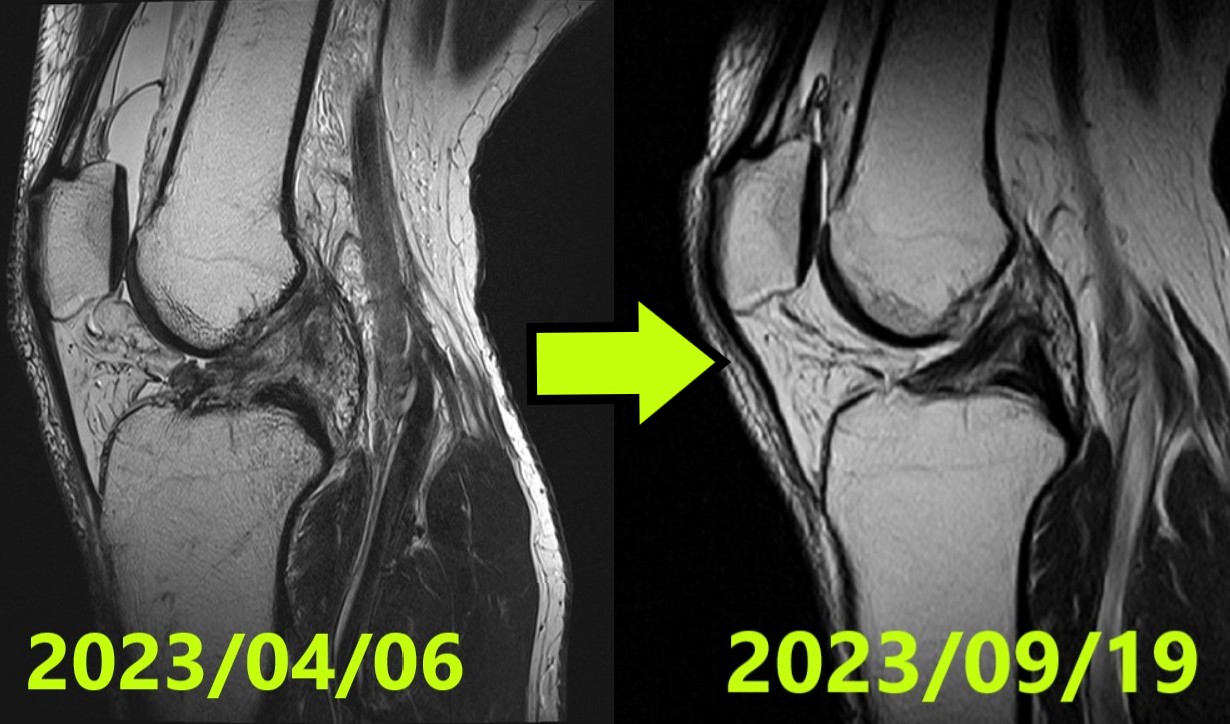

Caso de Curación Natural de LCA #50: Regeneración Perfecta (ACLOAS Grado 0) tras una Grave Ruptura Ihara Tipo IV

Ruptura completa del ligamento cruzado anterior (LCA) ocurrida durante un aterrizaje en snowboard. Siguiendo una estricta regla de consenso entre tres especialistas independientes, el diagnóstico inicial fue Ihara Tipo IV (la ruptura más grave y compleja). El paciente dominó de inmediato la «rotación externa completa de cadera» durante la asesoría online de Evo-Devo Exercise. A través de un manejo riguroso de la alineación (férula 0–30° / ≤3,000 pasos al día) y ejercicios constantes 3 veces al día, la resonancia magnética final obtuvo la calificación más alta posible: ACLOAS Grado 0 (regeneración de la estructura normal del ligamento). El paciente ha regresado con éxito a sus actividades diarias y ha iniciado un retorno gradual al deporte.

- Fecha: 6 de abril de 2023

- Diagnóstico: Ruptura completa de LCA rodilla izquierda

- Clasificación Ihara: IV (Grado 4) — Confirmada por consenso de 3 especialistas independientes

- Fecha: 19 de septiembre de 2023

- Evaluación: ACLOAS Grado 0 (regeneración de la estructura normal) — Confirmado por consenso de 3 especialistas independientes

- Resultado: El ligamento anteriormente roto logró una regeneración de alta calidad con una morfología idéntica a la de un ligamento sano

- Obtener un grado ACLOAS 0 partiendo de una clasificación «Ihara Tipo IV» (la más grave) representa un hito clínico extraordinario

- RM #1 (06/04/2023): Ihara IV — confirmada como grave ruptura completa por 3 especialistas

- RM #2 (19/09/2023): ACLOAS 0 — confirmada como regeneración de alta calidad por 3 especialistas

- Resultado: Un manejo preciso de la alineación permitió que incluso una ruptura de Tipo IV lograra el máximo grado de curación natural